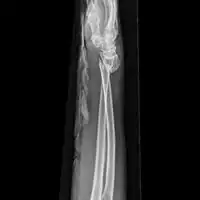

| Midshaft fracture of the radius and ulna | |